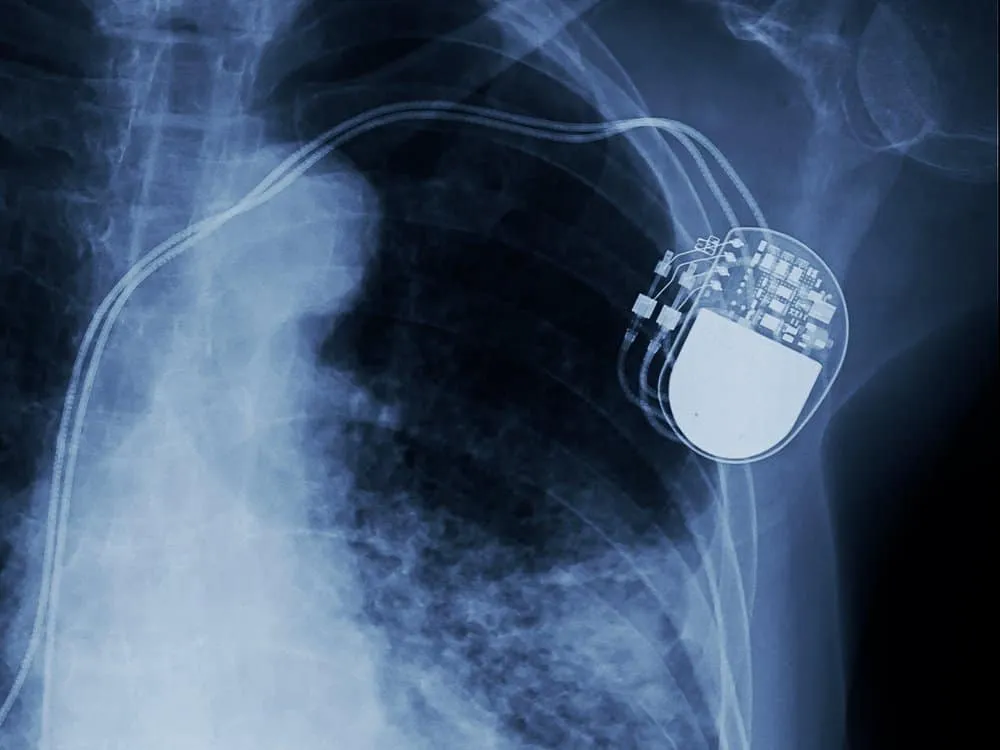

Máy trợ tim (còn được gọi theo chuyên môn là máy tạo nhịp tim) là một thiết bị nhỏ chạy bằng pin được đặt vào trong cơ thể (nằm dưới da ngực, trên cơ và xương thành ngực và phía dưới xương đòn trái) thông qua tiểu phẫu, để hỗ trợ hệ thống tạo nhịp và dẫn truyền trong tim. Tim có hệ thống điện tự tạo xung và dẫn truyền riêng để điều khiển nhịp tim. Tín hiệu điện (hay còn được gọi là các xung điện) di chuyển qua các buồng tim để cho biết khi nào tim cần phải đập (co bóp) đồng bộ để đẩy máu đi vào vòng tuần hoàn khắp cơ thể.

Hình ảnh siêu âm máy trợ tim được đặt vào trong cơ thể